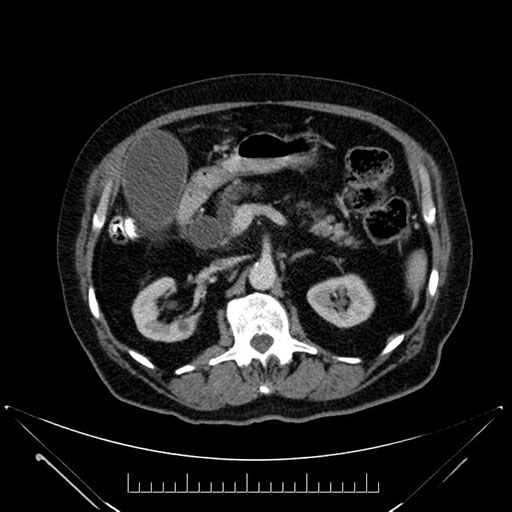

Whipple (pancreaticoduodenectomy) [case 7]

Imaging Analysis

Look through the patient's CT scan to identify any areas of concern for the necessary procedure.

Coronal - stented